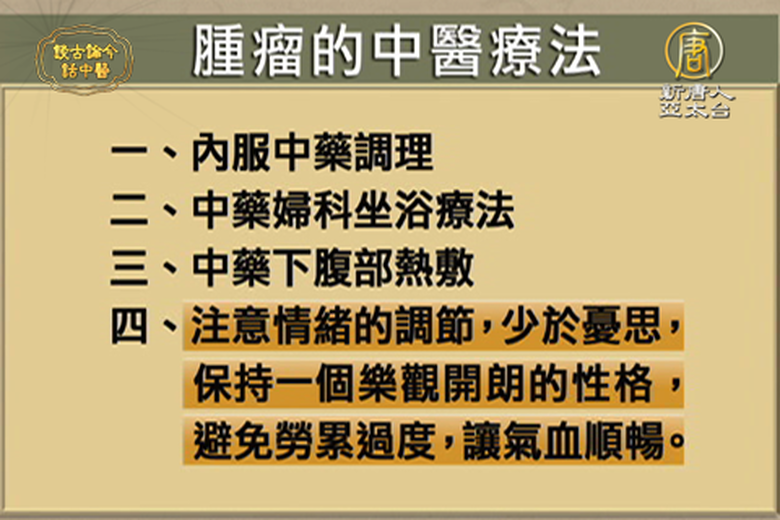

中醫治療腫瘤,有效嗎?

2016-11-24 15:54:42我們的環境存在著空氣污染、水污染,甚至日常食物,包括疏菜、水果、米飯等都潛藏著農藥殘留的問題。這些農藥或化學肥料在體內日久囤積,導致不能正常代謝,就會外顯為疔瘡、結癤、腫塊等症狀。

預防與治療癌症 中醫有獨到見解 |談古論今話中醫(56)

2021-06-30 12:31:29善待自己可以減少一半患癌症的機會。

中西醫結合治療癌症效果最佳 |談古論今話中醫(107)

2016-01-14 12:01:40癌症可以說是當今人類的一個最大的殺手。癌症患者除了按照一般的西醫治療之外,中醫對於癌症的治療效果又是如何呢?讓台灣中國醫藥大學教授林昭庚教授來告訴您